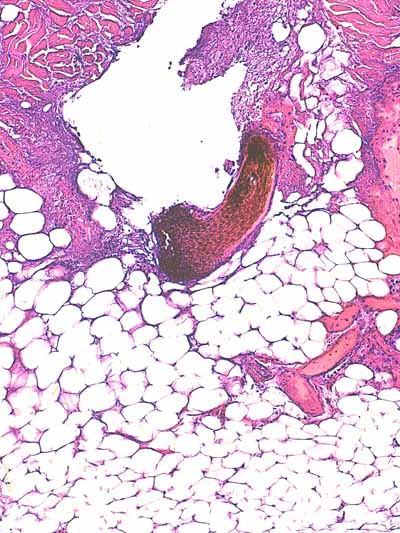

Photo 7 (Hémalun-Eosine X40) : l’hypoderme et le muscle peaucier sont dilacérés

par l’œdème et un infiltrat cellulaire diffus. Un vaisseau sanguin de moyen calibre contient un thrombus fibrineux.

Légendes de la Photo 7 :

- Flèches turquoises : muscle peaucier

- Flèches juanes : œdème et infiltrat neutrophilique dilacérant l’hypoderme et le muscle peaucier

- Ovale turquoise : la lumière d’une veine de moyen calibre est obstruée d’un thrombus fibrineux

- Double flèche verte : épaisseur dermique

- Double flèche bleue : épaisseur hypodermique

- Étoiles bleues : follicules pileux

Photo 8 (Hémalun-Eosine X100) : le muscle peaucier présente des zones de nécrose

de liquéfaction. Les lobules adipeux de l’hypoderme et les myofibrilles du muscle peaucier

sont dilacérés par un infiltrat exsudatif de granulocytes neutrophiles. La lumière

d’une veine de moyen calibre est obstruée par un thrombus fibrineux.

Légendes de la Photo 8 :

- Flèches jaunes : zone de nécrose de liquéfaction du muscle peaucier

- Flèches turquoises : œdème et infiltrat neutrophilique dilacérant les adipocytes des lobules adipeux de l’hypoderme

- Pointe de flèche turquoise : adipocyte

- Ovale turquoise : veine de moyen calibre

- Ronds verts : endothélium de la veine

- Ronds noirs : media de la veine

- Ronds bleus : adventice de la veine

- Double flèche bleue : hypoderme

- Étoile rouge : thrombus fibrineux ostruant la lumière de la veine

- Étoiles bleues : myofibrilles du muscle peaucier